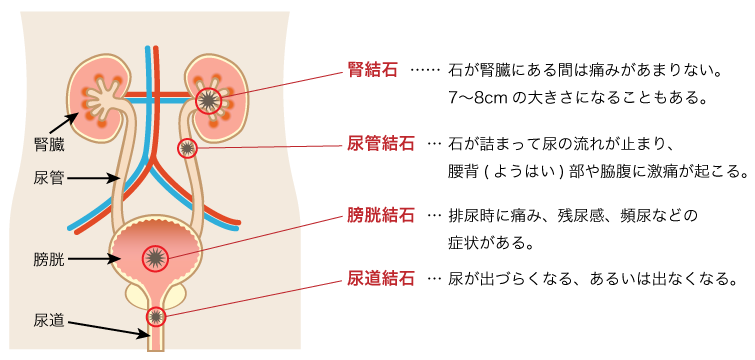

結石破砕治療の実際 – Radiology@Home。尿路結石の治療について | 医療法人社団實理会 東京国際大堀病院。尿路結石外来|尼崎市 おかだ腎泌尿器・ペインクリニック| 阪神。ぷっち おまとめ2袋 白米10キロ。尿路結石症(腎結石・尿管結石)の治療法 - 船橋クリニック 千葉。体外衝撃波結石破砕装置(ESWL)|焼津市立総合病院。尿路結石の検査 - 船橋クリニック 千葉県泌尿器科 尿路結石症。痛みを乗り越えた者だけが手にする秘宝商品説明これは単なる石ではありません。長きにわたり忍耐と痛みを経験した末、身体から生まれた奇跡の結晶です。賢者の石と呼ばれるにふさわしい、神秘的な輝きを放つ逸品!その力強い存在感は、あなたのコレクションに一層の深みを与えることでしょう。おすすめポイント•世界に一つだけのオリジナル品!•痛みを耐え抜いた歴史を感じられるストーリー付き•お守りやアクセサリーの材料にも最適こんな方におすすめ!•面白グッズ好きな方•他人とは違うコレクションを目指す方•人生の痛みを乗り越える象徴が欲しい方これを手にすることで、あなたも「賢者」の仲間入りを果たせるかも?一点限りの出品ですので、お見逃しなく!。尿管結石の最新治療技術 - Genspark。尿路結石症 – 社会医療法人 北腎会 坂泌尿器科千歳クリニック。尿管結石の最新治療技術 - Genspark。巨大腎結石への挑戦 | 研究報告 | 医療法人社団實理会 東京国際。尿路結石(尿管結石、腎臓結石、膀胱結石)の原因や治療について。尿路結石」について|市立貝塚病院